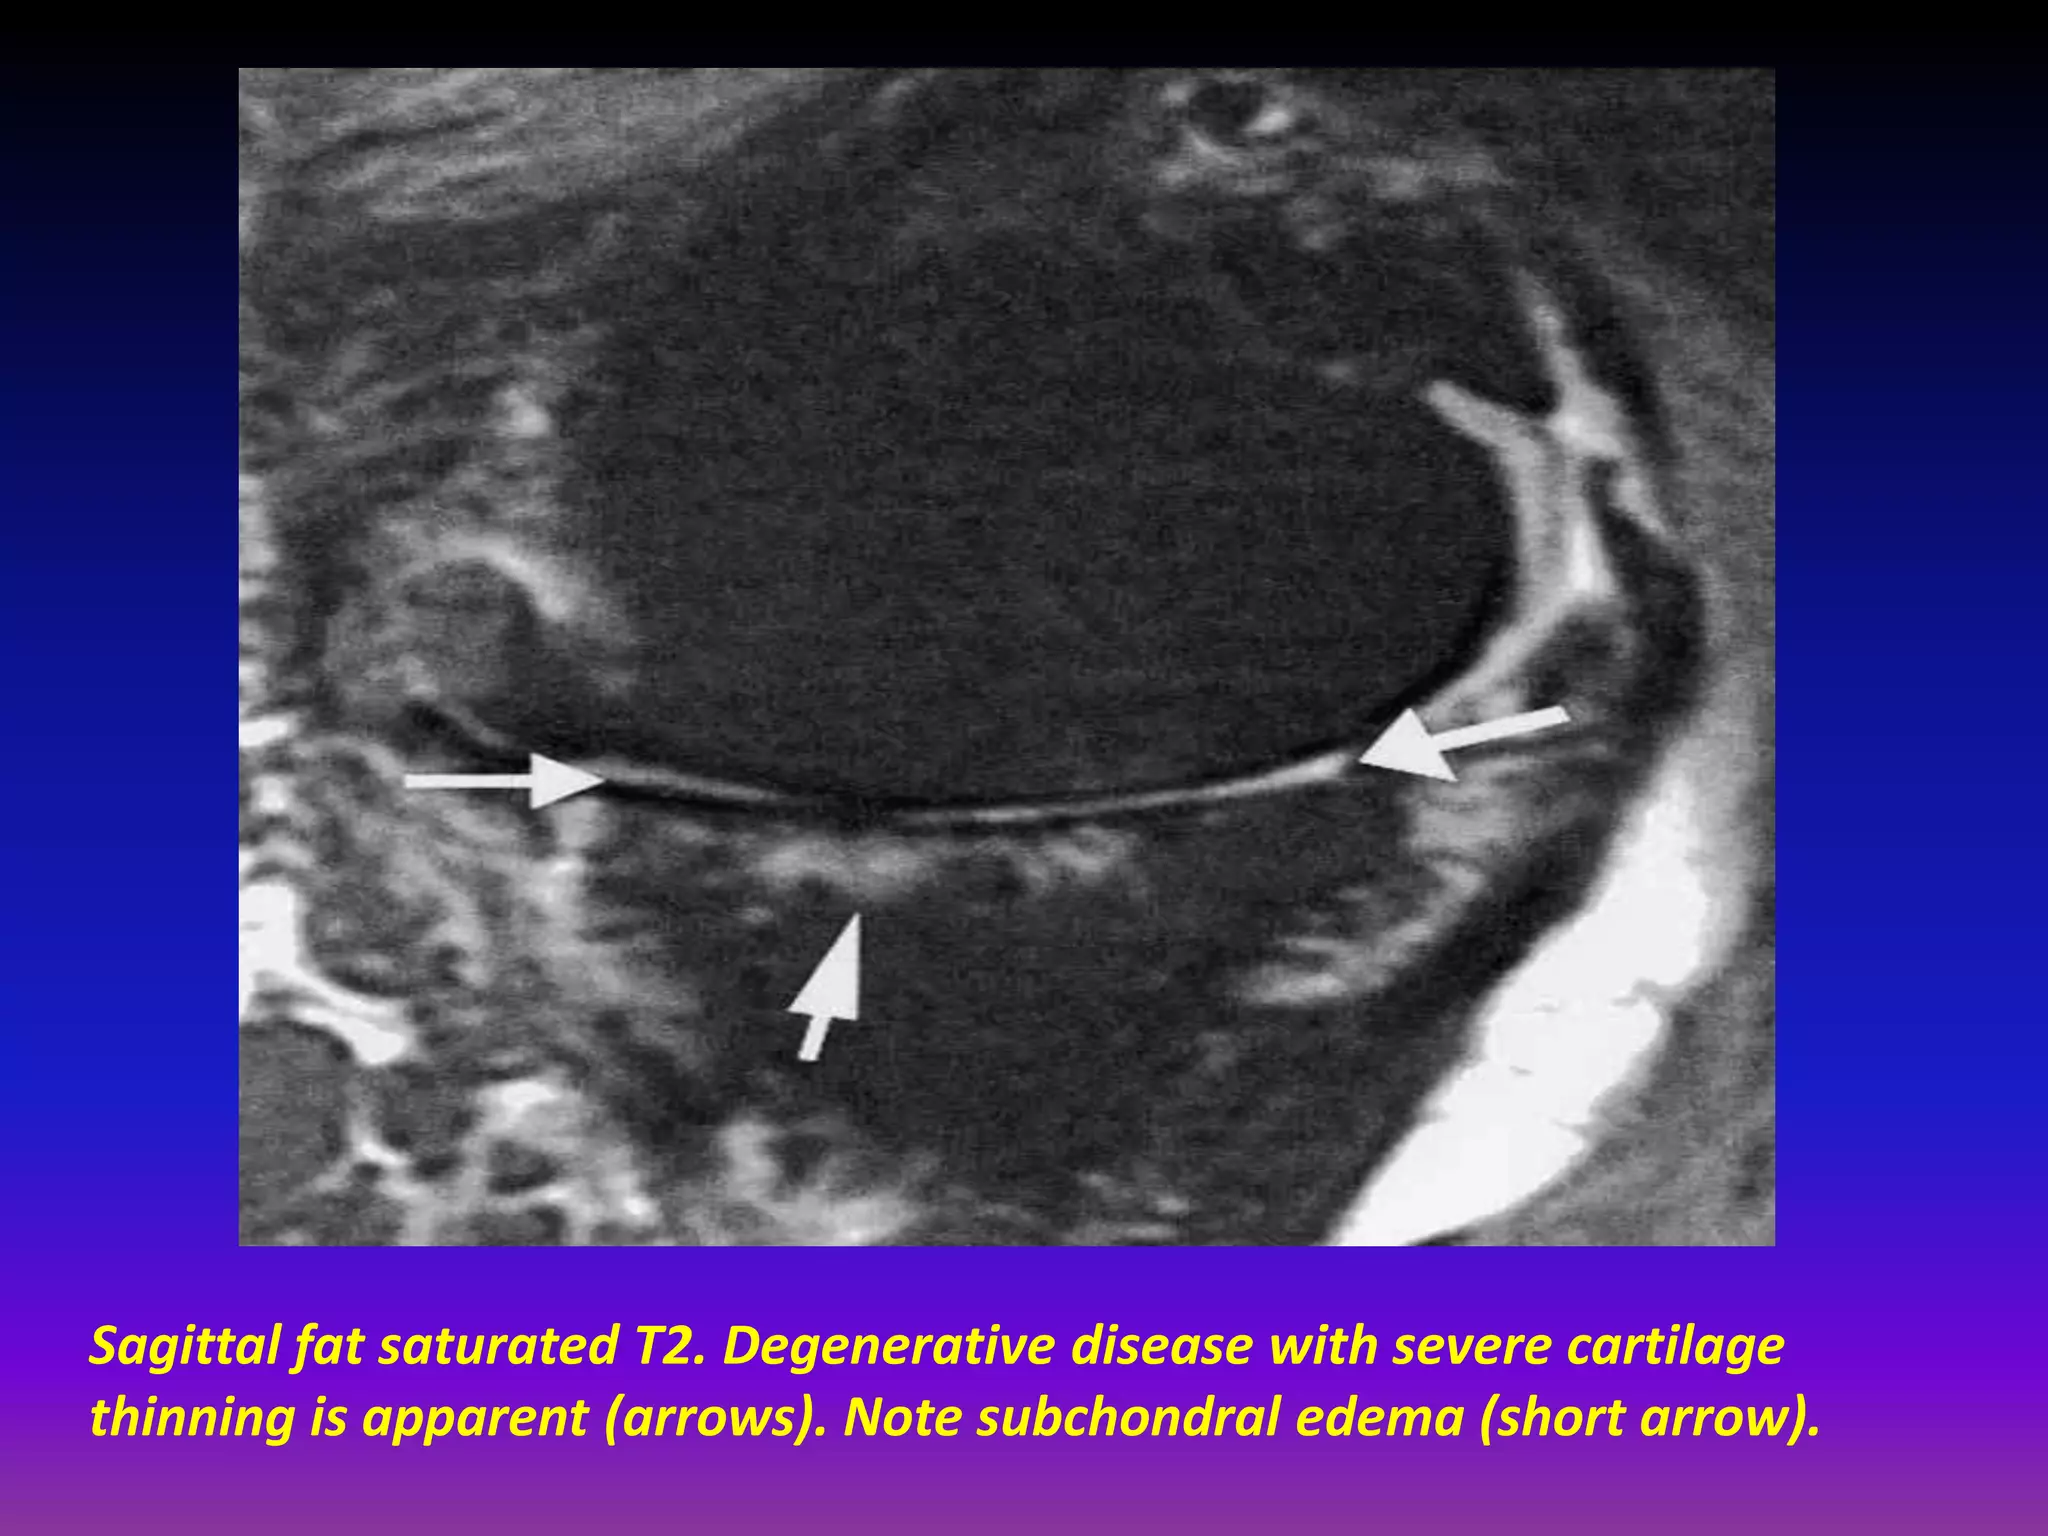

Sagittal fat saturated T2. Degenerative disease with severe cartilage

thinning is apparent (arrows). Note subchondral edema (short arrow).

Sagittal fat saturatedT2. Degenerative disease with severe cartilage thinning is apparent (arrows). Note subchondral edema (short arrow).